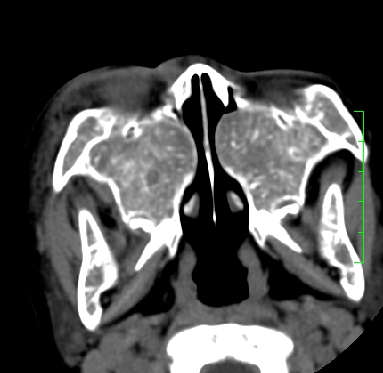

标题: PED1889:上颌窦病变

m,10y,外伤做ct

骨纤?

支持;骨纤,有皮肤色素沉着,性早熟时为albright综合征。

霉菌性鼻窦炎

骨化性纤维瘤可能性大。(与骨纤的鉴别:常见于面颅骨,多骨发病)